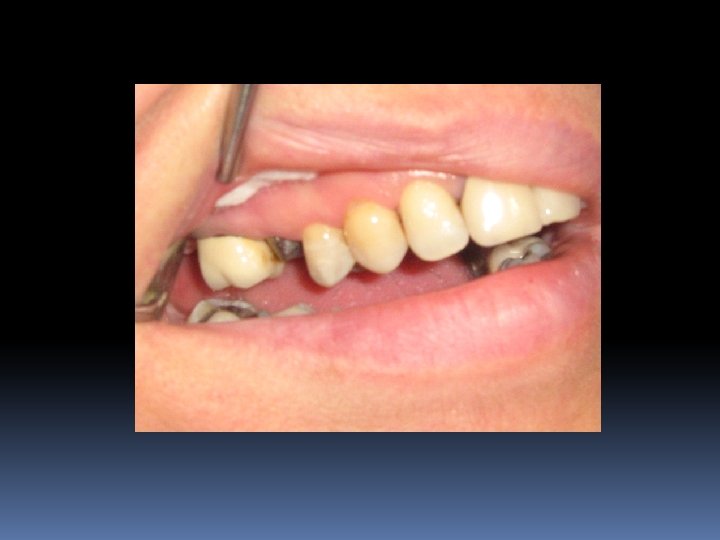

Ferrule effect (Ferrule Etkisi) Bir diş dokusunu saran kuvvetler demektir Eğer kron, kor yapının apikal marjinine kadar uzanır ve sağlam diş yapısını 360 derece sarar ise kron vertikal fraktürden korunmuş olur Yapının kırılmaması ve ferrule effect için en az 1 mm sağlam diş dokusu çepeçevre kron altında bulunmak zorundadır

Ferrule oluşturulmuş ve oluşturulmamış diş

Ferrule etkisi oluşturulmamış bir restorasyon çoğunlukla kök kırıklarına yol açar

Ferrule etkisi yaratmanın başka bir yolu da preperasyon basamağını dişetinin altına taşımaktır.

Ferrule etkisi yaratmanın 3. yolu periodontal cerrahi, 4. yolu ise ortodontik sürdürmedir.